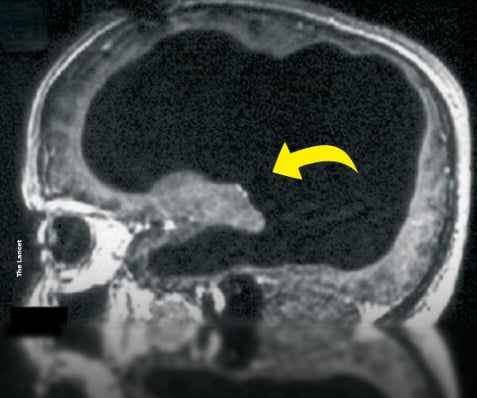

Ce qui ne devait être qu’une simple consultation médicale pour une gêne à la jambe s’est transformé en l’un des cas les plus fascinants de la neurologie moderne. Un fonctionnaire français, sans antécédents particuliers, s’est présenté chez son médecin pour un trouble bénin… avant que les examens ne révèlent quelque chose d’inimaginable : son cerveau n’occupait qu’environ 10 % de la cavité crânienne.

Les scanners ont montré que le reste de son crâne était rempli de liquide céphalo-rachidien, une situation généralement incompatible avec une vie normale. Et pourtant, cet homme menait une existence tout à fait ordinaire : marié, père de deux enfants, et employé de l’administration française.

Ce phénomène extrêmement rare est lié à une hydrocéphalie chronique, une accumulation lente et progressive de liquide dans le crâne. Chez cet homme, le processus s’était étalé sur des décennies, permettant à son cerveau de s’adapter peu à peu à cette pression interne.

Ce cas, publié dans la revue The Lancet, continue d’intriguer les chercheurs. Il remet en question une idée centrale de la neurologie : quelle quantité de matière cérébrale est réellement nécessaire pour penser, ressentir et être conscient ?